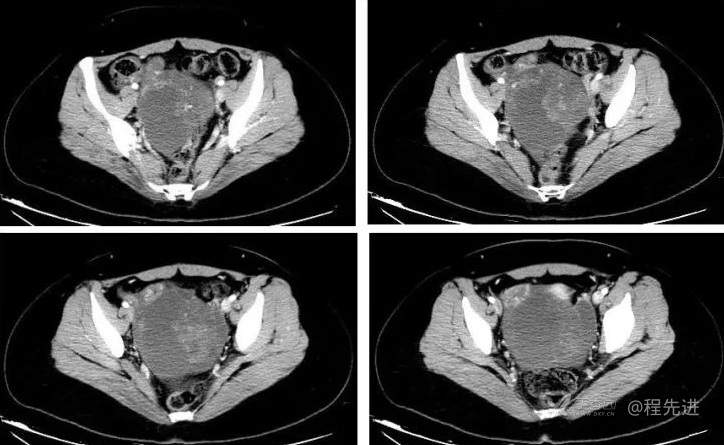

阴式彩超:子宫前位,大小47*51*28mm,形态规则内膜厚7mm。左侧类似卵巢大小32*27mm,右侧卵巢大小25*18mm,子宫偏右侧可见105*94*76mm混合回声包块,与右侧卵巢分界不清,有包膜,内以液暗区为主,夹杂可见范围约51*40mm不规则稍高回声团,隐约可见将类似左侧卵巢包裹其中。另子宫偏左侧可探及一大小38*32mm囊性肿块,边界清,壁薄光滑,内透声好,后壁效应增强。CDFI: 混合回声包块未见明显彩流。囊性肿块内未见明显血流信号。盆腔内子宫直肠窝探及23mm液暗区

提示:子宫偏右侧混合回声包块,疑占位性病变,炎性包块待排,子宫偏左侧囊性肿块,盆腔积液。